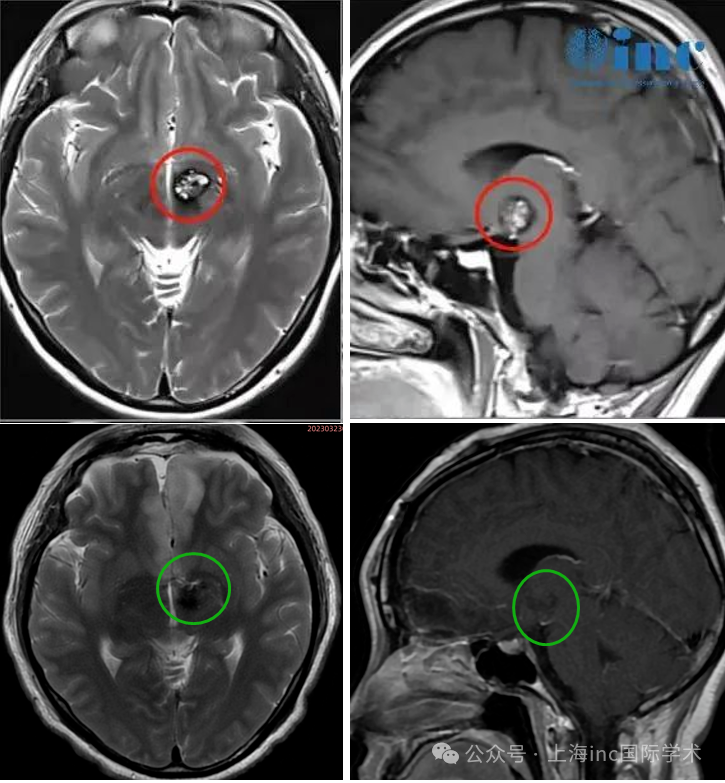

术前术后影像对比

从2022年3月检查出丘脑海绵状血管瘤到巴教授成功为文文手术切除病变,一年期间,文文经历了两次出血,症状甚至不断加重,眩晕呕吐、右眼视力下降明显,右下肢无力,步态不稳,肢体麻木……

术后4个月文文恢复良好,肢体活动自如